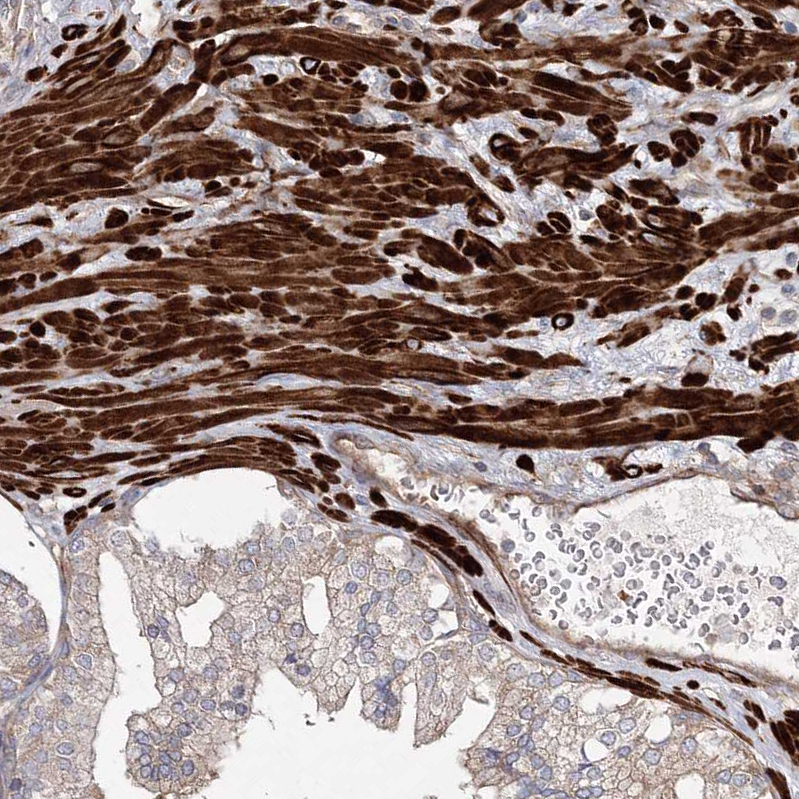

Immunohistochemical staining of human duodenum shows strong cytoplasmic positivity in smooth muscle cells.